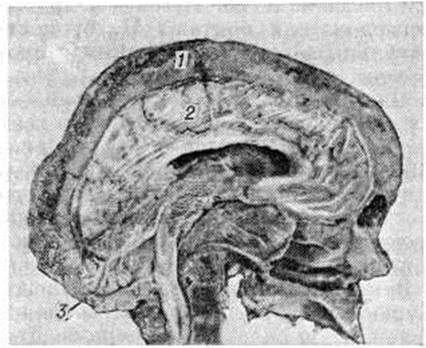

Рис. 1.

Сагиттальный распил черепа при болезни Педжета: утолщение, неравномерный склероз и разрежение костей мозгового черепа (1); головной мозг (2) сдавлен, «распластан» на уплощённом основании черепа; задняя черепная ямка резко углублена вследствие прогибания затылочной кости (3). Анатомо-топографические соотношения между костями черепа и головным мозгом нарушены.

При поражении черепа процесс чаще начинается с лобной кости и распространяется на теменную, теменно-височную и затылочную области.

Кости лицевого черепа поражаются сравнительно редко. Заболевание характеризуется возникновением на ограниченном участке кости очага из волокнистой остеогенной ткани и простейших, слабо обызвествленных губчатых структур. Постепенное увеличение зоны поражения приводит к утолщению, спонгиозированию костей, изменению величины и формы черепа (рисунок 1). Выраженность патологический изменений у разных больных неодинакова. Поверхность поражённого отдела кости красноватая, под периостом видны множественные мелкие отверстия сосудистых каналов. Рисунок кровеносных сосудов на внутренней поверхности костей черепа сохранен. Изменённая кость достигает 3—6 сантиметров толщины. На распиле видны поля остеосклероза (смотри полный свод знаний), участки разрежения костных структур, островки кроветворной и жировой ткани. В костях черепа преобладают однородные мелкоячеистые структуры, в большем количестве располагающиеся на внутренней костной пластинке (рисунок 2). Анатомо-топографические соотношения между костями черепа постепенно нарушаются. Передняя черепная ямка, скат основания черепа уплощаются (платибазия), боковые отделы средней ямки и задняя черепная ямка прогибаются, затылочная кость оседает на заднюю дугу атланта.

Верхний отдел позвоночника смещает кверху скат основания черепа (базилярная импрессия). В итоге все отделы основания черепа провисают вокруг внедряющегося эндокраниально позвоночного столба (конвексобазия).